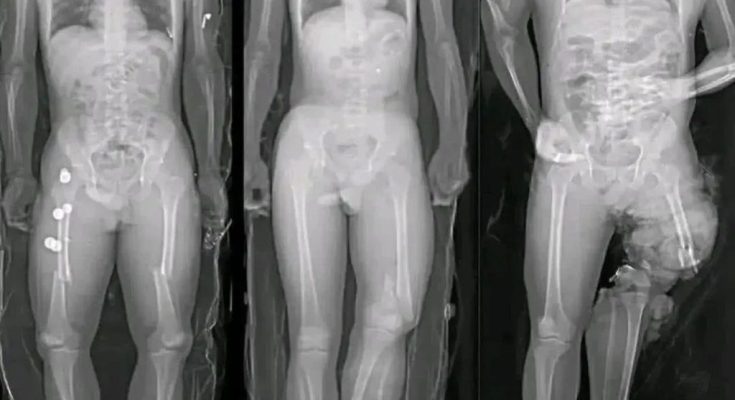

One of the most common claims in viral posts is that COVID vaccines “damage the heart.” This statement oversimplifies and distorts a complex medical issue.

Medical research has identified a small number of myocarditis cases—an inflammation of the heart muscle—following certain mRNA vaccines, particularly among adolescent and young adult males. However, context is critical. These cases are rare, typically mild, and most individuals recover fully with minimal treatment.

Multiple peer-reviewed studies show that the risk of myocarditis from COVID infection itself is significantly higher than the risk associated with vaccination. COVID-19 as a disease has been linked to more severe cardiac complications, including inflammation, blood clots, and long-term heart damage.

In other words, when comparing risks, vaccination reduces overall heart-related danger rather than increasing it.